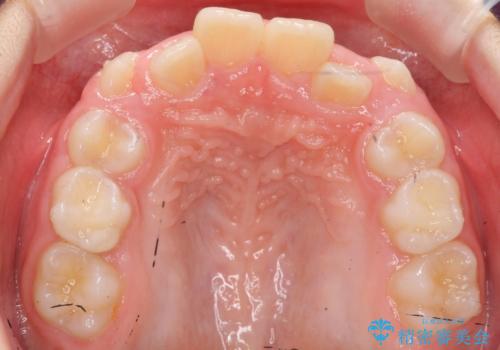

八重歯 歯を抜かずにインビザラインで

- 八重歯を主訴に来院。

抜かずに歯を少し削って入れる方法で並べました。

10代のうちに矯正をしておくと歯の移動は簡単で、歯ぐきも下がりにくいです。